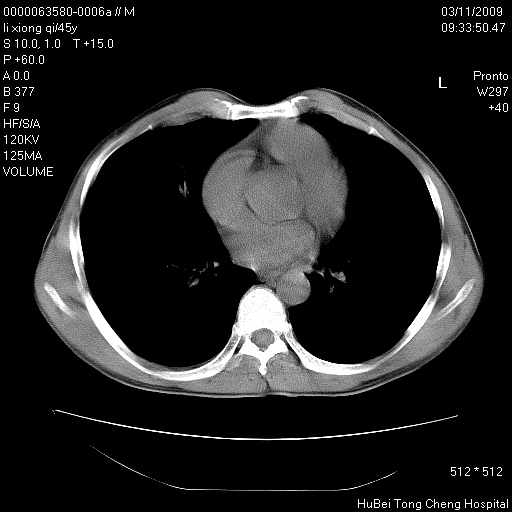

患者 男,45岁。胸痛,咳嗽伴痰中带血1月余。

临床诊断:肺结核?

胸部ct轴位平扫(层厚10mm,螺距1.5,重建间隔10mm),图像如下:

考虑肝癌肺转移